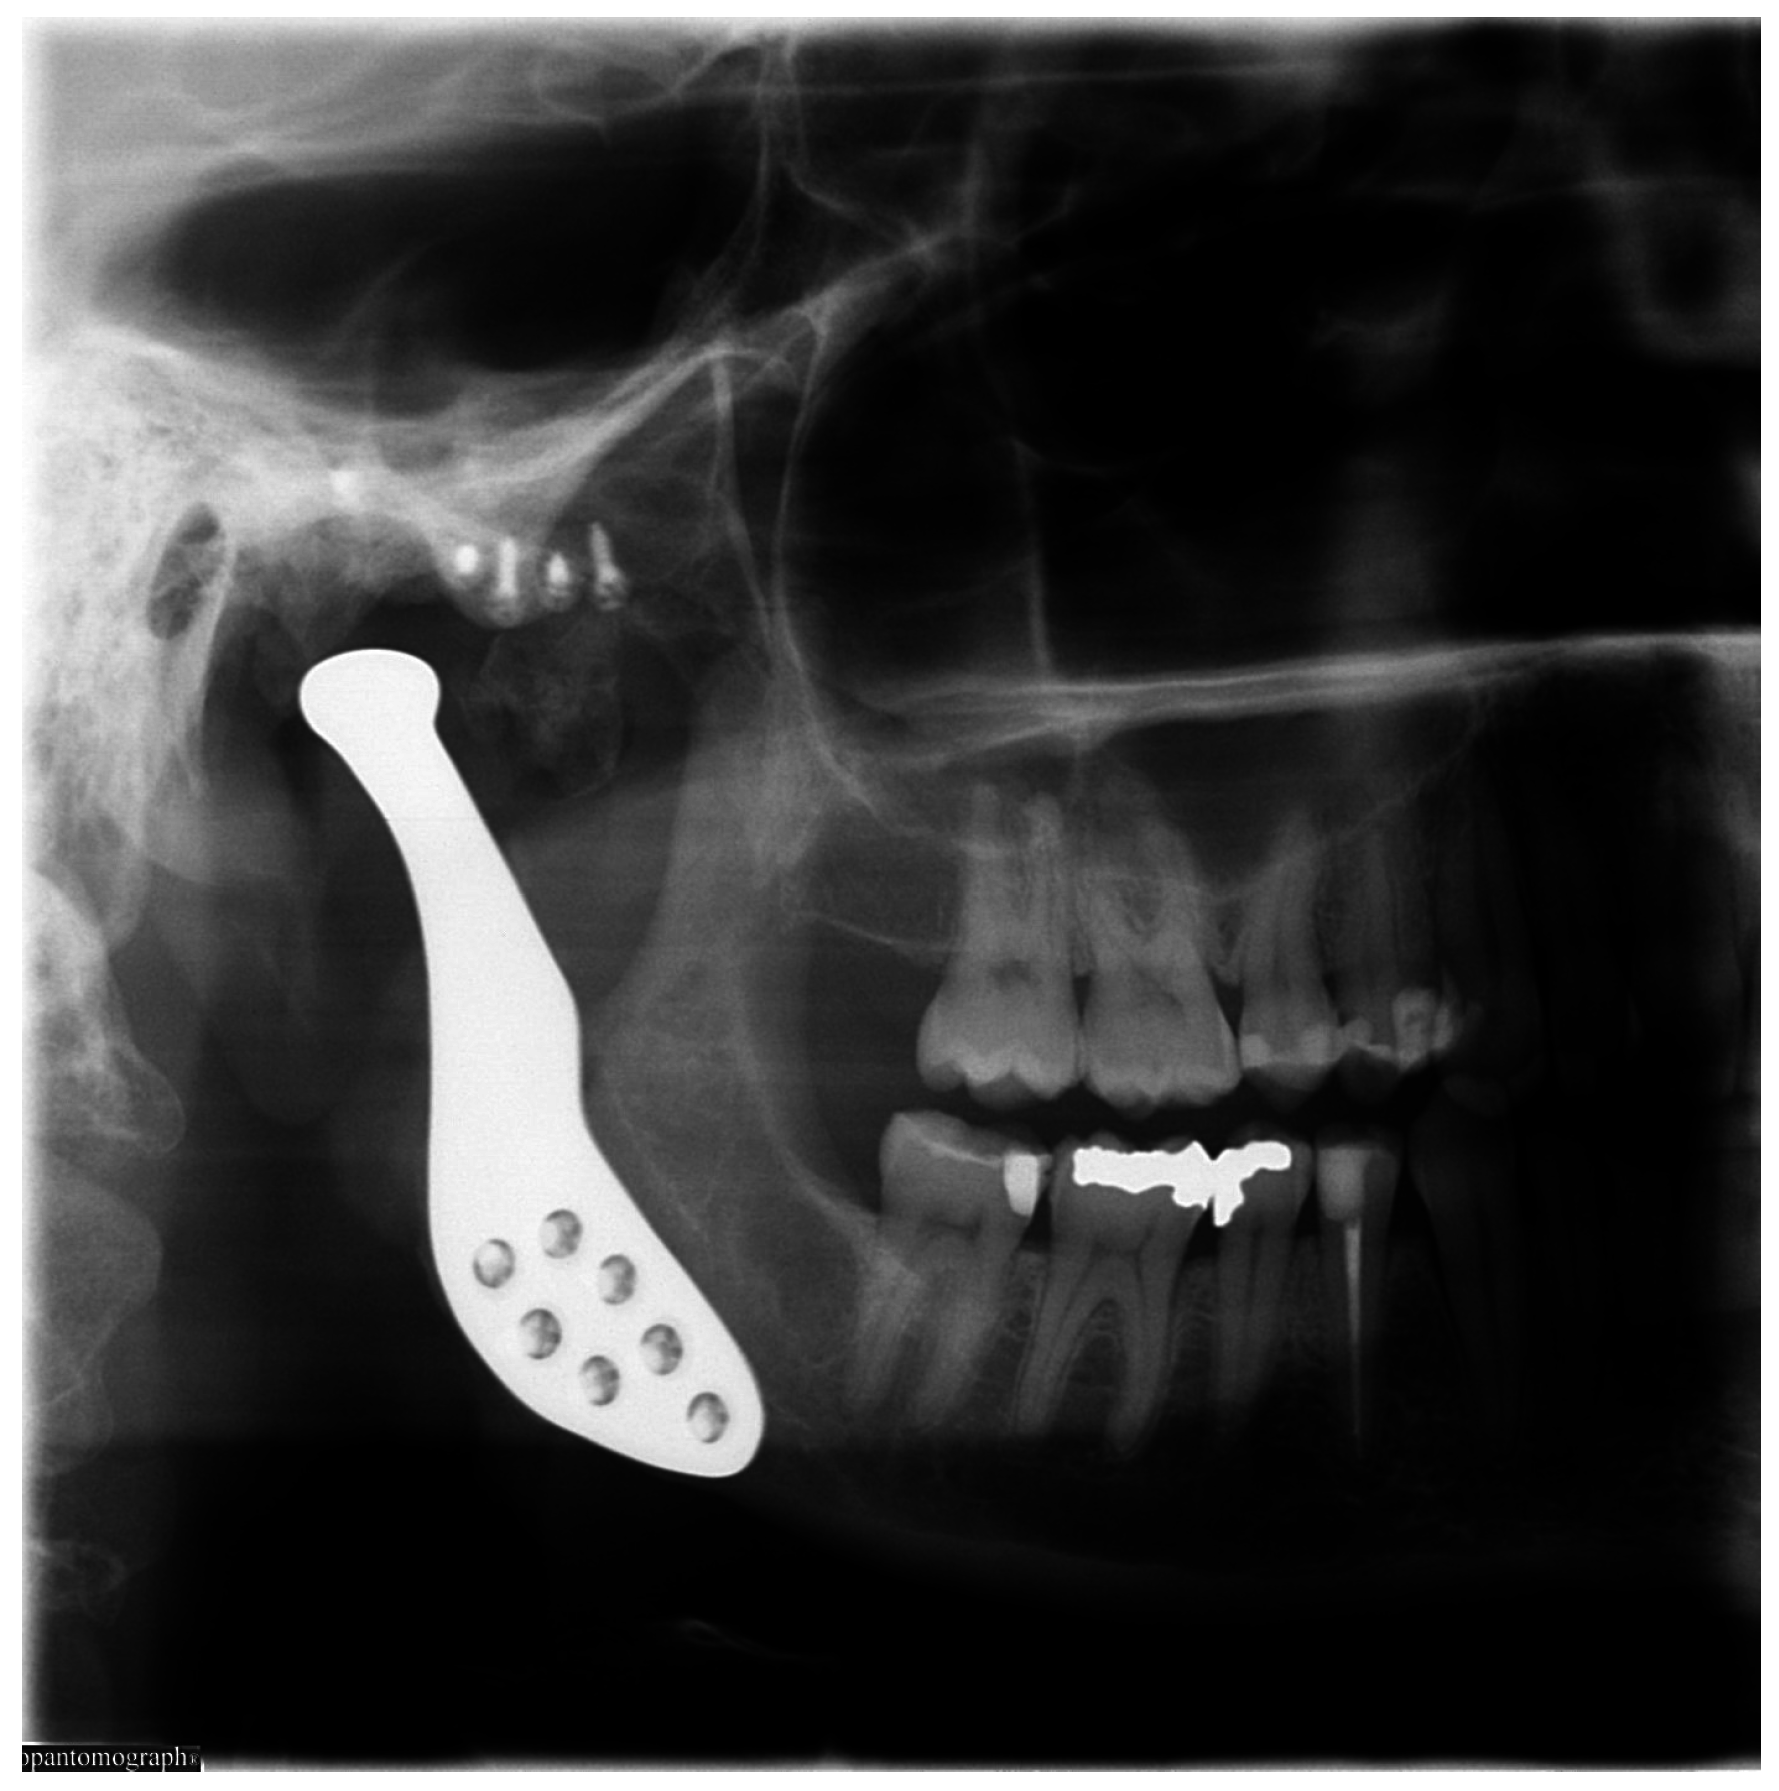

From dental-scan.co.uk

💀 Degenerative Joint Disease November 02, 2022 Dental Scan Ltd Dental Bone Degeneration In an exciting new study, scientists have been able to combine biological and mechanical techniques to repair and regenerate bone and. Jaw bone deterioration is a severe condition that can cause many problems for your oral health. It’s essential to know the symptoms and how to get treatment. If your doctor deems that a bone graft is right for you,. Dental Bone Degeneration.